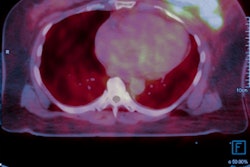

A broad approach can sometimes be beneficial in molecular imaging. New research from one of the leading centers for cancer imaging in Europe has found that PET/CT and MRI are better together for predicting patient outcomes in cervical cancer.

A group from Leeds Teaching Hospitals NHS Trust in the U.K. reported that the combination was more accurate than either modality alone for assessing response after chemotherapy in cases of locally advanced cervical carcinoma. Prof. Andy Scarsbrook, a consultant radiologist and nuclear medicine physician at St James's University Hospital and professor of radiology at the University of Leeds, served as one of the co-authors on the award-winning study.